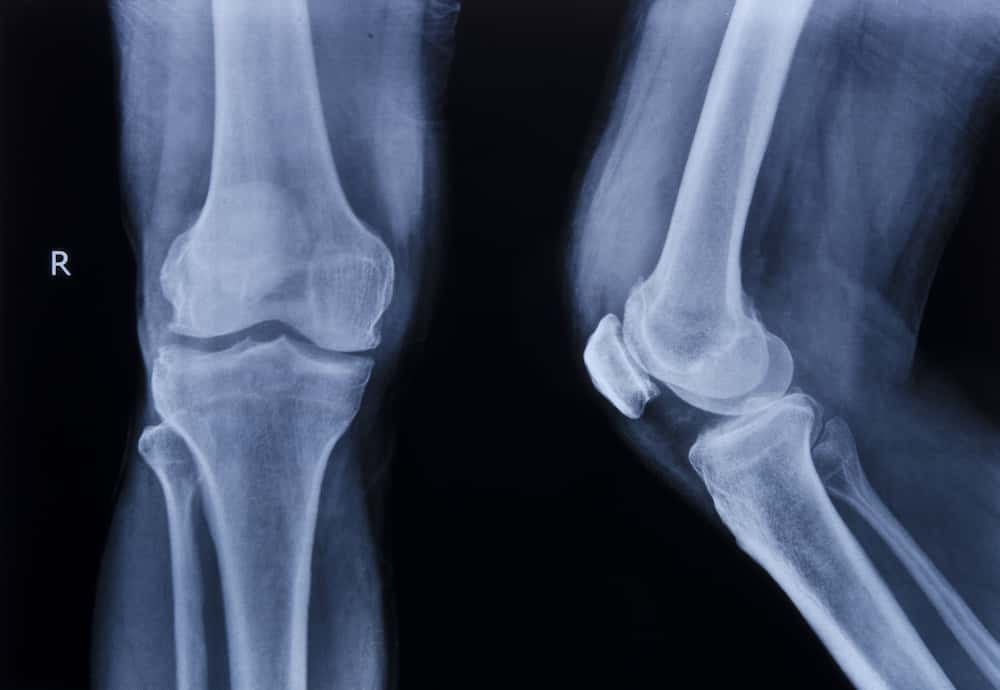

In most cases, osteoarthritis can be suspected or diagnosed through the clinical features (what it looks like and how it behaves), your symptoms (what you tell us about your knee) and the clinical assessment (testing the movements etc.). An X-ray of the knee is often used to help diagnose osteoarthritis but is not always required.

In a lot of cases, the information we as healthcare professionals can get from asking you questions and testing the knee is enough to make a decision. X-rays are a very useful tool as they show you what your knee looks like on the inside. however, in some cases what your knee looks like on the inside doesn’t really marry up with what your problem might be.

There is growing evidence (experiments and clinical studies) that demonstrate what you see is not always what you get with X-rays and scans, and that a lot of the so-called ‘worn out’ or ‘abnormal’ findings are seen commonly in people with no pain, stiffness or symptoms.